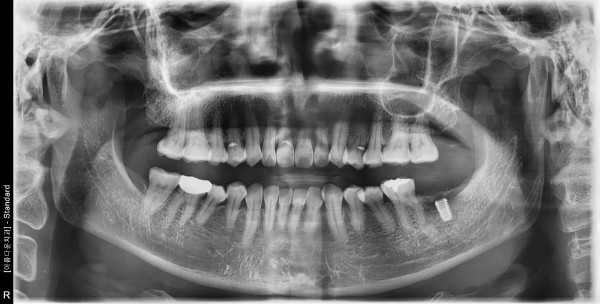

51세 여자환자 / 좌측하악 발치후 뼈이식및임플란트식립